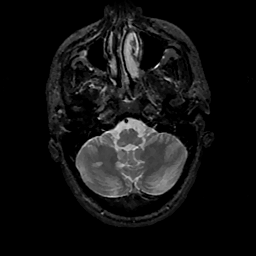

MR Study #11, May 5, 1991 -- Slice #9

[Home][Help][Clinical][Tour 1][Tour 2] Slice 9